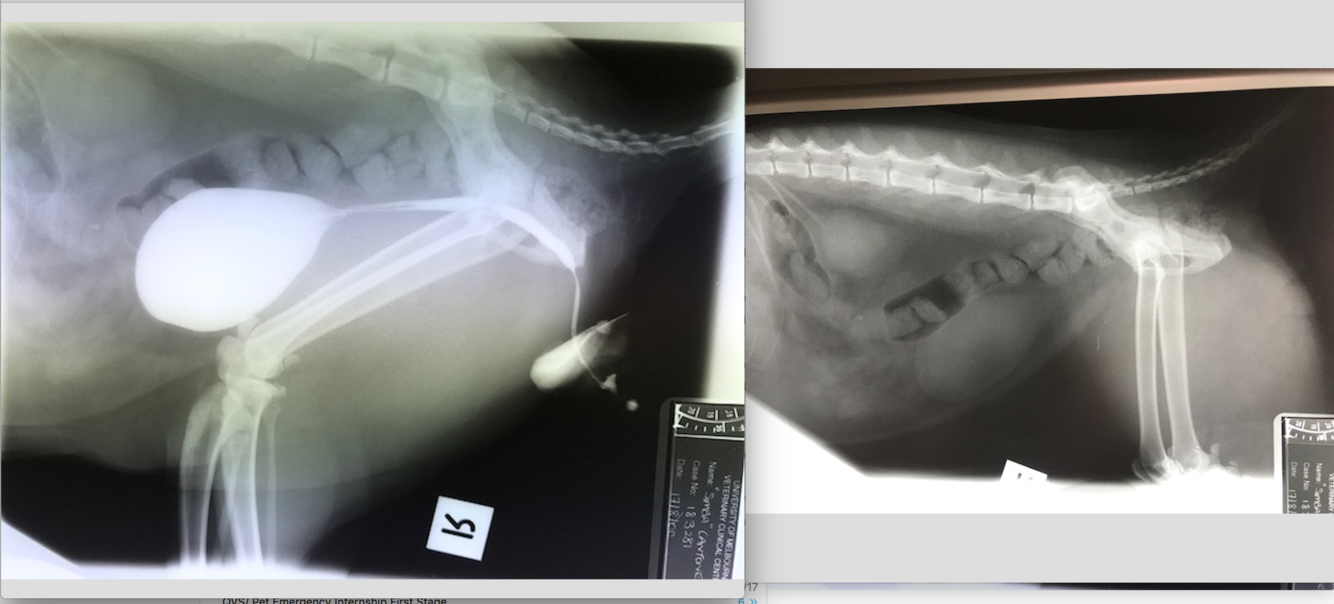

9 week old Male Labrador

Hx: Vomiting and anorexia for 2 days

HR 144 RR 36 Temp 39.7C NAD on abdo palpation

* Why decreased serosal detail?

* The gas within the GIT– which parts contain gas? Are the gas filled portions of the GIT over distended?

* The fluid filled portions– which parts contain fluid? Are they over distended?

* Which other organs can you ID? Are these within normal limits?

* What are your recommendations for further investigation and treatment of Baughie?

Should not exceed 1.6 times the height of the centre of the body of L5 at its narrowest point.

SI/L5 ratio of 1.7 for diagnosis of intestinal obstruction (sens and spec only 66%)